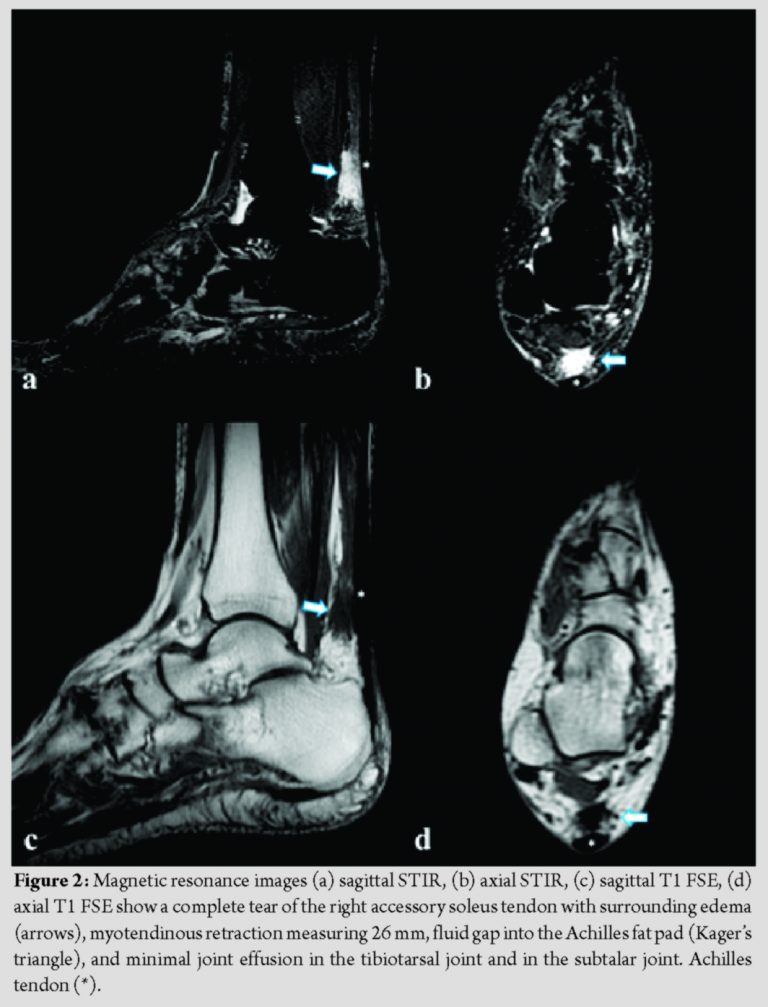

US evaluation of the calf and ankle was subsequently performed showing normal findings of the Achilles tendon, soleus muscle, plantaris tendon, and both medial and lateral heads of the gastrocnemius; color Doppler US excluded deep vein thrombosis. However, examination of the posteromedial region showed fluid gap with a myotendinous retraction suspicious for an accessory soleus tear muscles with a complete tear of tendon with a myotendinous retraction (Fig. 1). MRI confirmed the diagnosis and demonstrated complete tear of the right accessory soleus tendon with surrounding edema, myotendinous retraction measuring 26 mm, fluid gap into the Achilles fat pad (Kager’s triangle), and minimal joint effusion in the tibiotarsal joint and in the subtalar joint (Fig. 2). No other abnormalities were detected on MRI.